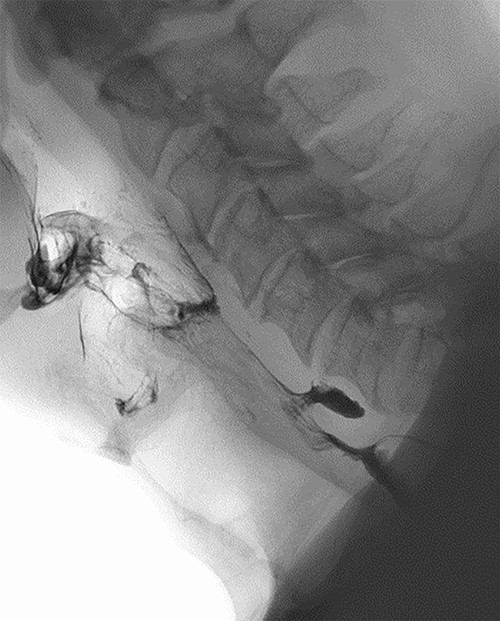

Clinical and radiological findings were reviewed in a multidisciplinary setting where features were suspicious for ZD as an underlying aetiology. This was confirmed on barium swallow which demonstrated a 1.1-cm ZD (Fig. 3).